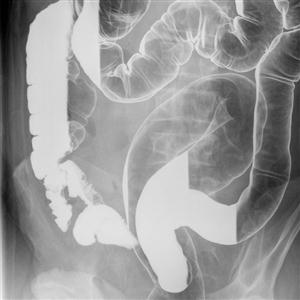

1)Barium Studies :

• c) Barium Enema (Mainly for large intestine) In Children and Adults.